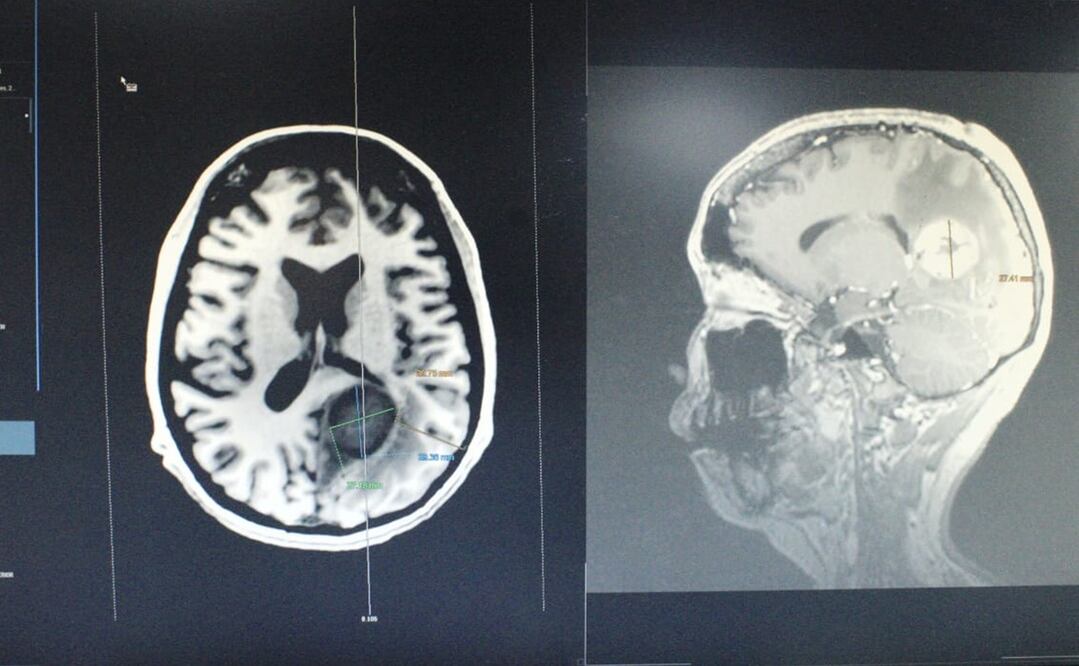

Un grupo multidisciplinario de médicos especialistas del Instituto de Seguridad y Servicios Sociales de los Trabajadores del Estado (ISSSTE) retiraron exitosamente un tumor cerebral maligno del tamaño de un huevo a una mujer de 34 años.

La operación se realizó en del Centro Médico Nacional (CMN) “20 de Noviembre”, duró cinco horas, y participaron cinco especialistas, un anestesiólogo y dos enfermeras especialistas, que lograron extirpar con éxito el tumor que se localizaba del lado izquierdo en la zona profunda del cerebro.

El diagnóstico de la paciente, cuya identidad no fue revelada, era una metástasis de cáncer tipo leiomiosarcoma desarrollado en el corazón. El tumor, informó el ISSSTE comprometía estructuras relacionadas con lenguaje, comprensión, cálculo y función visual.